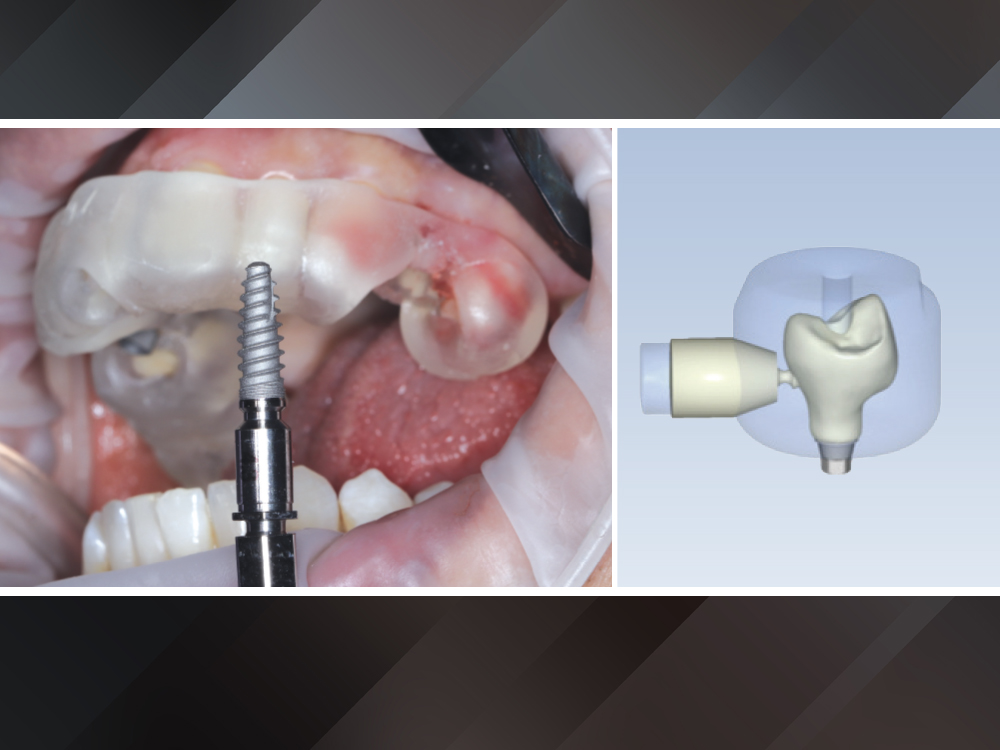

Once verified, the restorations were sent to the fastmill.io unit for fabrication

Figure 10: Once verified, the restorations were sent to the fastmill.io unit for fabrication. The compact mill, which operates without an external air compressor — making it quieter than other in-office mills on the market — was loaded with the BruxZir NOW SRC blocks.

The fastmill.io unit milled each restoration in approximately thirty-five minutes

Because the zirconia is fully sintered, no oven firing, sintering, or glazing cycle was required

Figures 11a, 11b: The fastmill.io unit milled each restoration in approximately thirty-five minutes. Because the zirconia is fully sintered, no oven firing, sintering, or glazing cycle was required. After light polishing utilizing the BruxZirAdjustment & Polishing Kit (Glidewell Direct), the crowns were ready for delivery the same day.